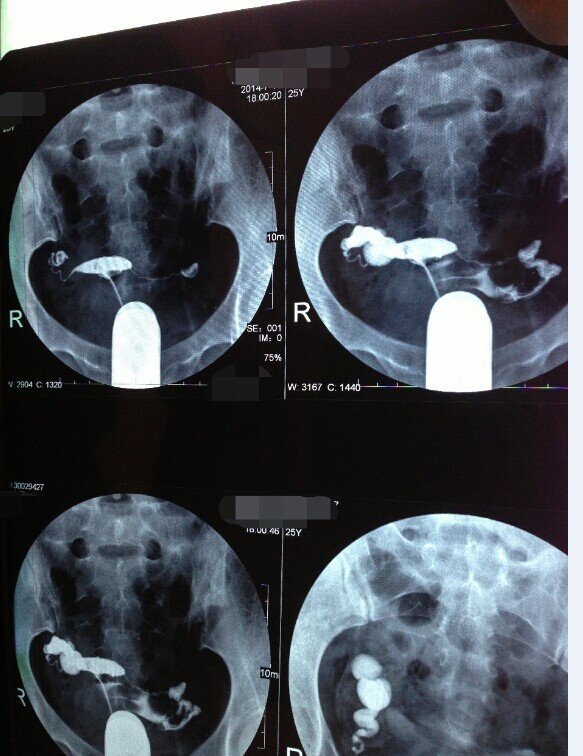

一边输卵管积水一边畅而不通 医生让我去做试管 难道真的到了要做试管的地步么?求懂的好心人帮忙看看 点击展开 匿名用户 2014-07-20 19:51 满意回答 可以先试试宫腹腔镜疏通,不行再做试管。通而不畅比较好疏通的,积水药过不室耻严重也好抽水,具体根据个人情况,找称挡截个有经验的专家问问。 烟红香_pOX1 2014-07-21 08:45 宝宝知道提示您:回答为网友贡献,仅供参考。 为您推荐: 其他回答 是的,要先结扎,在取卵,,试管 匿名用户 2014-07-20 20:16 相关问题 我右边输卵管以前宫外孕切断了的 左边现在是远端堵塞伴有积水 医生叫我做试管 请问试管真的是最佳 请问,32周检查出来有并脑积水,怎么办,好心人,又是试管婴儿 我是盆腔炎导致输卵管堵塞,引起不孕不育,医生断定我只有做试管婴儿,可是我自然怀孕了,生了宝宝,如果